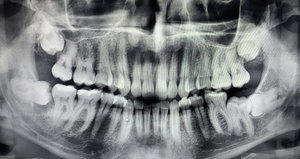

Мне 23 года. Сделала панорамный снимок, оказалось, что зуб мудрости находится в горизонтальном положении. Нужна операция, корень проходит через лицевой нерв. Насколько удаление опасно? Будет ли он в таком положении и дальше, или начнет беспокоить уже в скором времени?

• Вам необходимо сделать 3-d снимок, так как в случае ортопантомограммы возможно наложение кадров. Нижнечелюстной канал может располагаться щелочной или лингвальные относительно зуба мудрости. В случае травмы нижнего луночкового нерва возможно онемение половины челюсти, губы, щеки и т.д.

По жалобе на 6-ку был сделан рентген, на снимке был обнаружен сюрприз в виде 8-ки. Сколько зуб сидит под десной ― неизвестно, так как дискомфорта не ощущаю. Хочу поинтересоваться ― насколько сложное предстоит удаление?

• Удаление предстоит сложное, а также дискомфорт при реабилитации 2-3 дня. Главное, чтобы данную манипуляцию проводил дипломированный хирург с постоянным опытом удаления ретинированных зубов. Рекомендую Вам записаться к нам на прием к хирургу Хачумян В.Х., и обещаю Вам качественный результат без патологий.